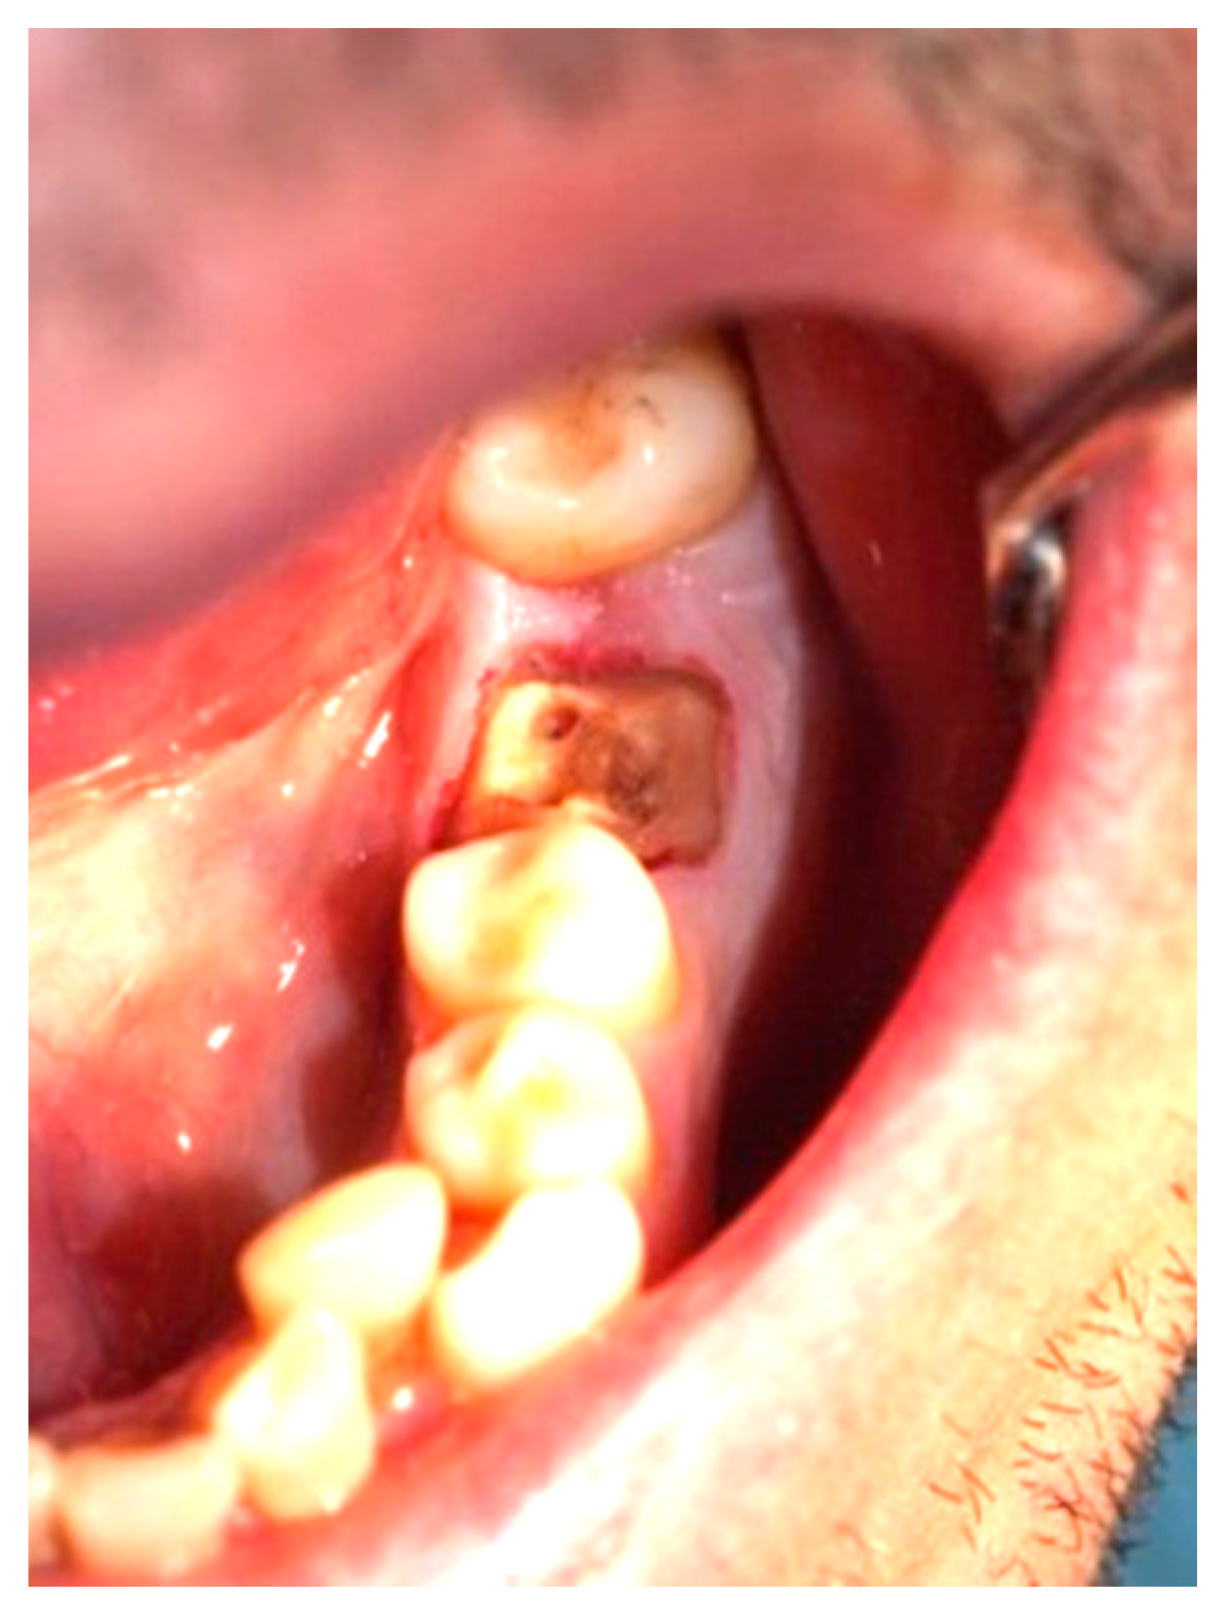

Figure 3, Figure 4, Figure 5, Figure 6, Figure 7 and Figure 8 display the follow-up of the healing process after a resective procedure for lengthening a short clinical crown with a laser.

Figure 4.

Healing at the 24th hour: the wound was covered with fibrinous plaque and an erythematous halo.

Figure 5.

Healing at the 72nd hour: the wound was covered with fibrinous plaque and an erythematous halo.